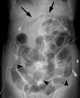

Bowel obstruction, also known as intestinal obstruction, is a mechanical or functional obstruction of the intestines which prevents the normal movement of the products of digestion. Either the small bowel or large bowel may be affected. [Source: Wikipedia ]